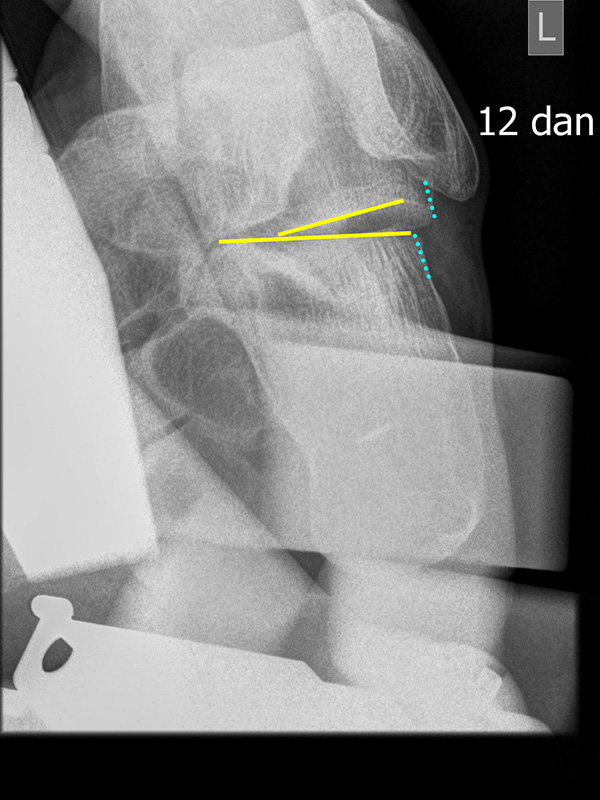

TMT-1-Gelenk lateral (Tarsometatarsale-1-Gelenk)

In der Seitaufnahme wird eine plantare Öffnung des TMT-1-Gelenks als Indikator für eine Instabilität gewertet. Coughlin et al. 5 definierten einen Winkel zwischen der proximalen Gelenkfläche des Os metatarsale I (gelb) und der distalen Gelenkfläche des Os cuneiforme I (rot). (Norm: ±0° 5).